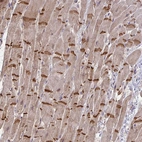

Immunohistochemistry analysis in human cerebral cortex and liver tissues using HPA059445 antibody. Corresponding SLC9A6 RNA-seq data are presented for the same tissues.